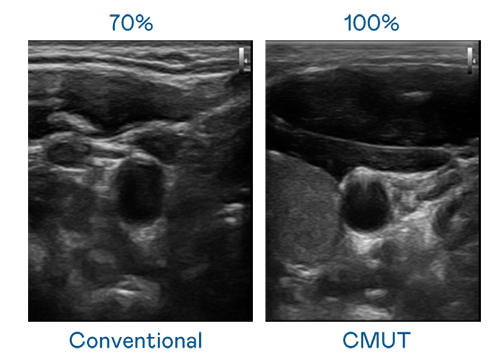

CMUT 技術是一種用電容式微機電元件來產生超音波訊號的技術。與傳統 PZT 壓電式技術相比,CMUT 頻寬增加 30%,更寬頻的超音波訊號讓影像解析度大幅提升,是實現高影像品質醫療超音波掃描、促進精準醫療發展的關鍵技術。

超音波影像的解析度高低,首先取決於探頭能發出的訊號頻寬。利来w66 CMUT 可提供高清晰的超音波訊號,提供高頻寬、高靈敏度、影像紋理細節更高的超音波影像,協助醫護人員縮短影像判讀時間及利用精準的醫療影像進行診斷。